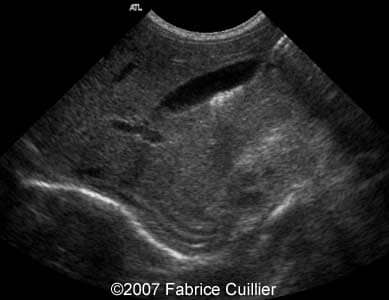

A 30-year-old patient, G3P2, was referred to our clinic at 36 weeks of gestational age after hyperechoic foci were seen in the fetal gallbladder on ultrasound. 13- and 22-week sonographic examinations were unremarkable. The 36-week ultrasound evaluation was normal except for an elongated echogenic mass seen in the gallbladder (Images 1A, 1B, 1C, 1D). Neither ascites nor hydrops were seen. The gallbladder appearance was identical on sonographic re-evaluation at 37 weeks GA (Images 3A, 3B). At 38 weeks of gestational age, a healthy female infant weighing 3200 g was born. There was no evidence of hematologic incompatibility, sepsis, or jaundice. Laboratory values including those for the cystic fibrosis gene, hemoglobinopathy, and liver functions were normal. On the fifth day of life, ultrasound was performed, showing a gallbladder of normal size containing several gallstones (Images 5A, 5B, 5C, 5D).

Images 1A, 1B. Transverse abdominal section at 36 weeks of gestational age through the fetal abdomen demonstrating a long, non-shadowing echogenic mass within the gallbladder.

1A

1B